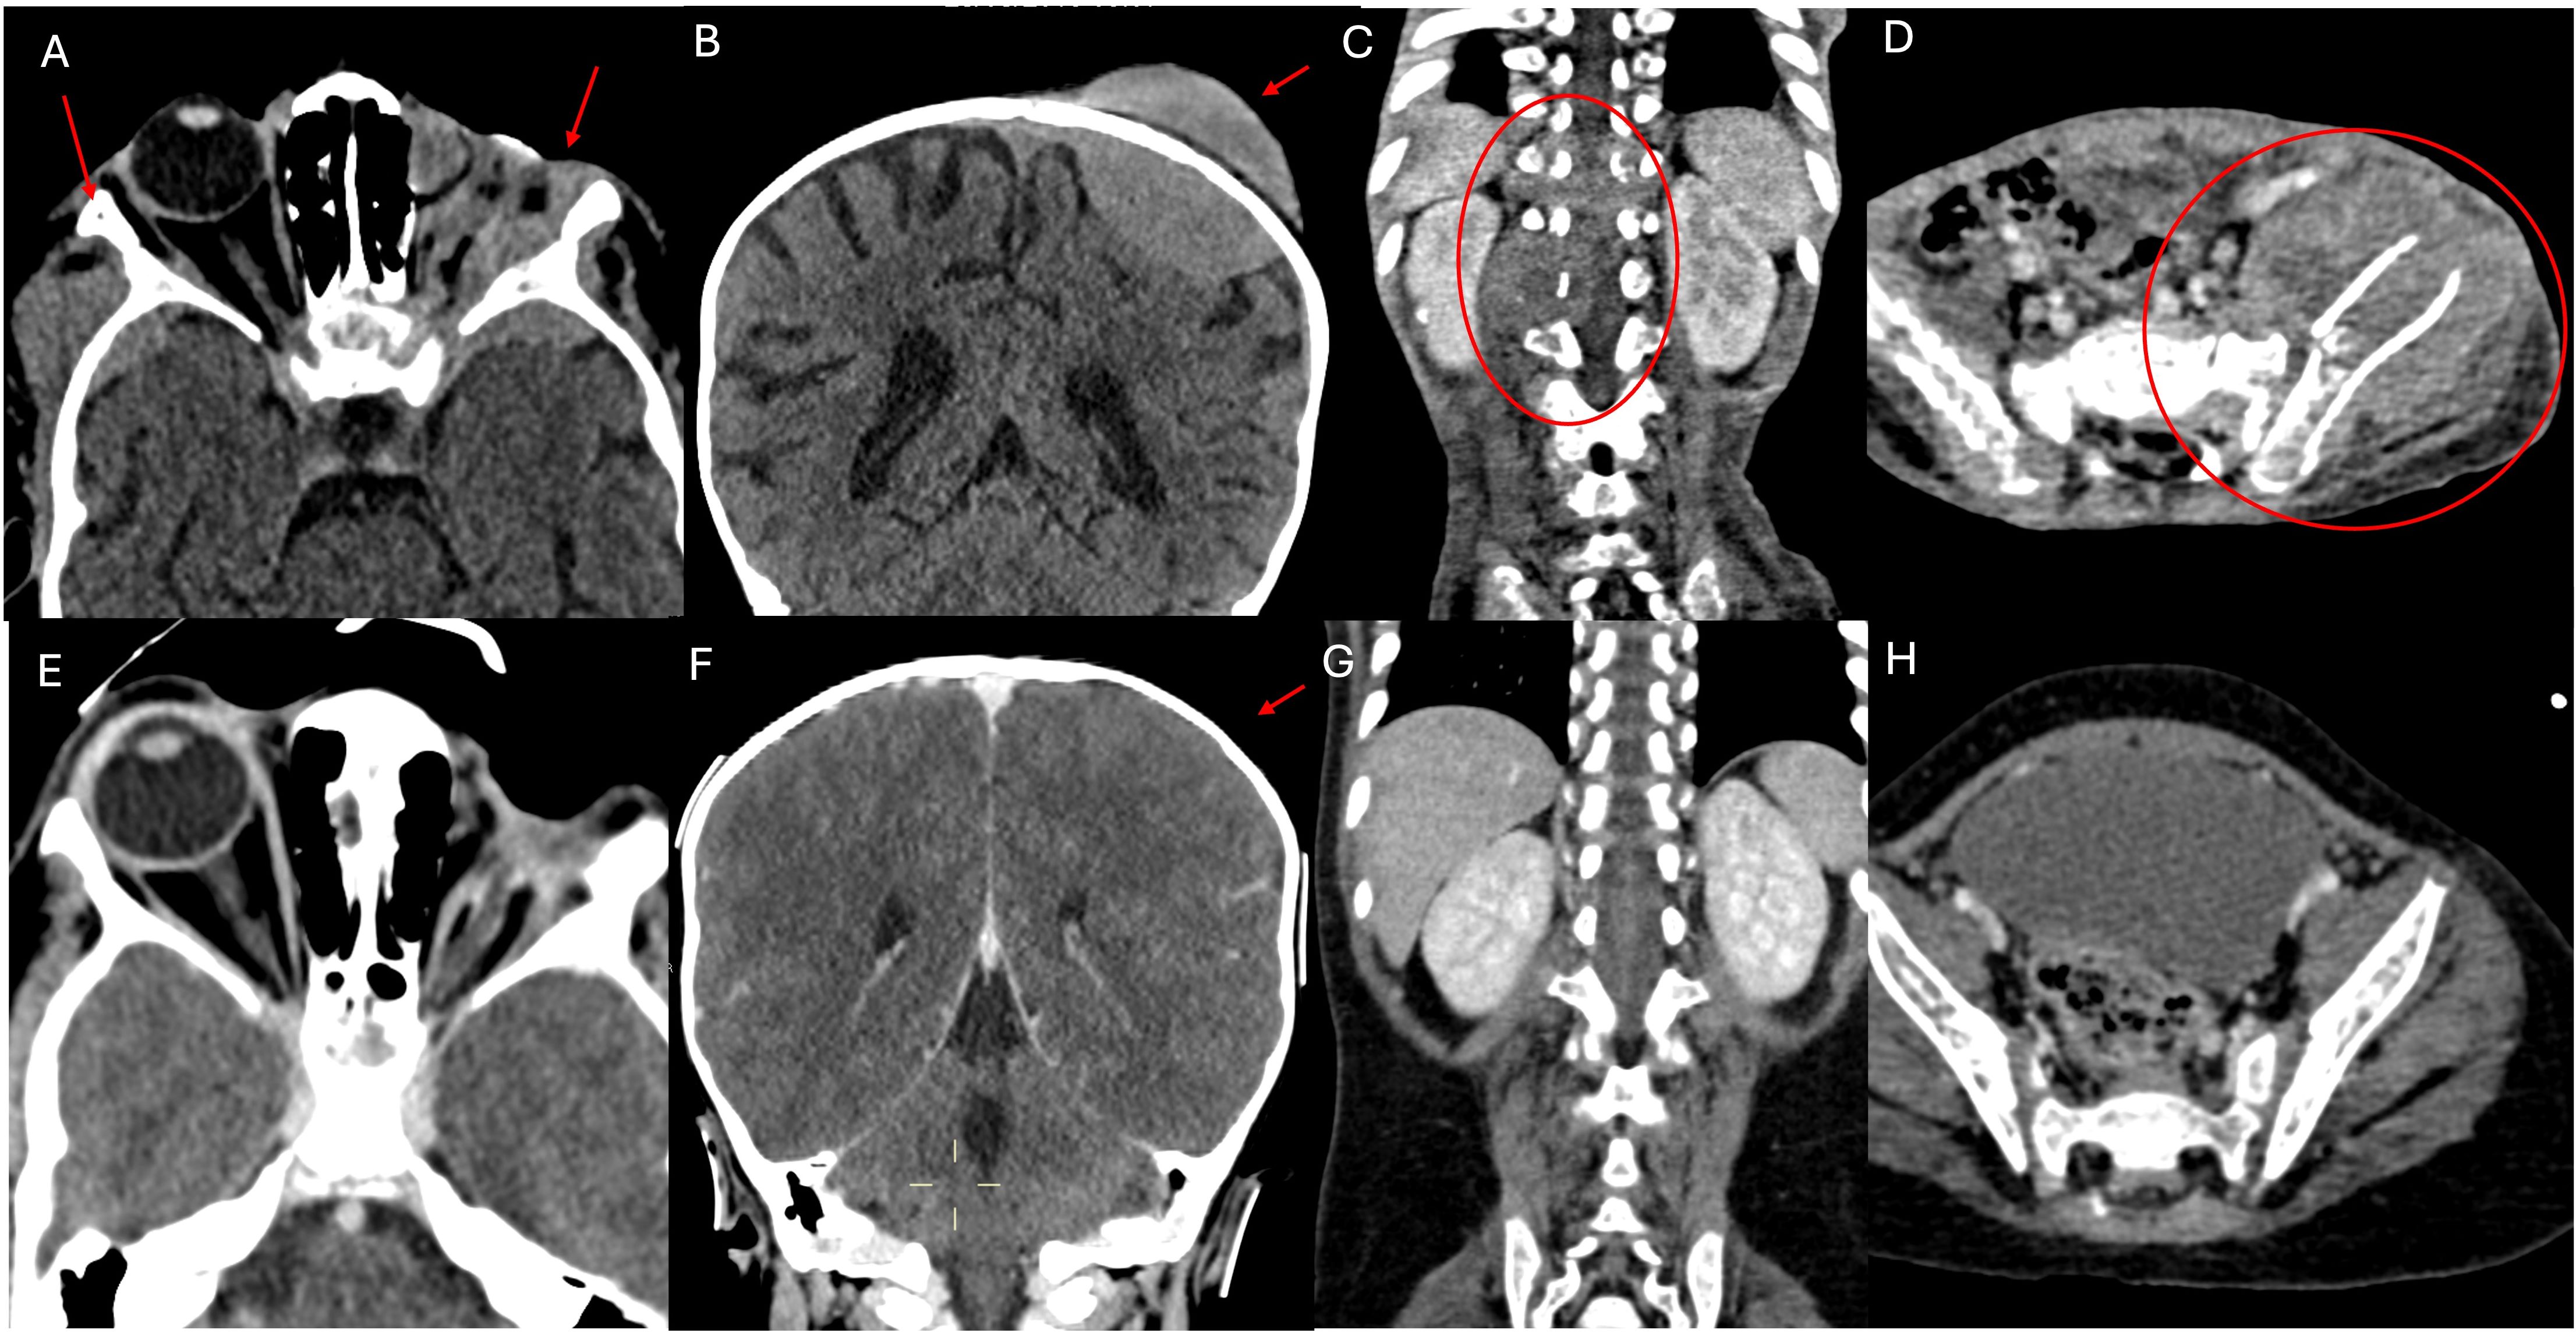

A 2-year-old boy was referred to our Hospital with a suspected diagnosis of RB in the left eye. Prior to admission, the patient had undergone orbital exenteration. At the clinical visit, the patient was in poor general condition, with severe malnutrition, generalized bone pain, and limb weakness. A total body CT scan revealed massive extraocular disease extension involving the left orbit and multifocal skeletal lesions (Figures 1A–D). A biopsy of a lesion in the right shoulder confirmed the diagnosis of RB. Molecular analysis of the tumor tissue demonstrated a homozygous pathogenic mutation in the Rb1 gene (c.1959dup). FISH analysis showed a normal copy number of the MYCN gene. The bone marrow biopsy showed infiltration by malignant cells. GD2 expression levels in the CD45-negative cells of the fresh tumor biopsy sample were quantified by flow cytometry and found to be 79.7% (Figure 2). Brain and spine MRI showed no evidence of parenchymal or leptomeningeal disease. Cerebrospinal fluid (CSF) analysis was negative for tumor cells. The patient initiated systemic chemotherapy - ICE regimen (Ifosfamide 3gr/mq day 1-2-3, Carboplatin 750mg/mq day 1, Etoposide 150mg/m2 day 1-2-3)-, combined with intrathecal Topotecan (0.4 mg/dose) for CNS prophylaxis. Restaging after four cycles, including whole-body CT and brain and spinal MRI, demonstrated a good partial remission of left orbital and bone lesions. The patient’s general condition progressively improved, including regained mobility and adequate nutritional intake. Constitutional genetic testing for germline Rb1 alterations was negative. Afterwards the patient underwent HDC according to the COG ARET 0321 protocol (Carboplatin 350mg/mq day 1-2-3/Thiotepa 300mg/mq day 4-5-6/Etoposide 250mg/mq day 4-5-6) followed by ASCT (1). No moderate or severe complications during treatment. Post- HDC whole-body CT imaging showed no radiological evidence of residual disease (Figures 1E–H). We did not administer radiotherapy to the sites of bulky disease due to the patient’s young age. Given the high disease burden at diagnosis and the expression of GD2 on tumor cells, anti-GD2 mAb-Db was initiated 60 days after HDC, aiming to replicate the results previously achieved in MRD, following an approach analogous to HR-NB protocols. Three cycles were administered on a compassionate use basis, following informed consent for off-label therapy. The dosing schedule was 100 mg/m² over 10 days, every 5 weeks. Supportive care included morphine and gabapentin. Dinutuximab beta was well tolerated with no serious adverse effects. At the latest follow-up, the patient is in complete remission, with an overall survival of 6 years since diagnosis.

Figure 1. CT scan examination. The first section documents numerous metastatic localizations. (A) shows pathological iperdense tissue with high contrast enhancement involving the soft tissues of the left orbit (site of enucleation surgery for RB), infiltrating the local bony structures (greater wings of the sphenoid, frontal and temporal bones), and extending bilaterally to the middle cranial fossa. The left optic nerve is not recognizable, also due to the limited resolution of the CT scan for soft tissues. (B) shows an osteodural metastatic localization with high contrast enhancement of the cranial vault on the left side (parietal bone). (C, D) respectively show a partially lytic paravertebral mass extending into the spinal canal and a mass centered in the left iliac bone, partially lytic and associated with a fracture, extending to the iliac muscle, both indicative of metastases. (E–H) shown the almost complete disappearance of extraorbital metastatic lesions at the end of the treatment.